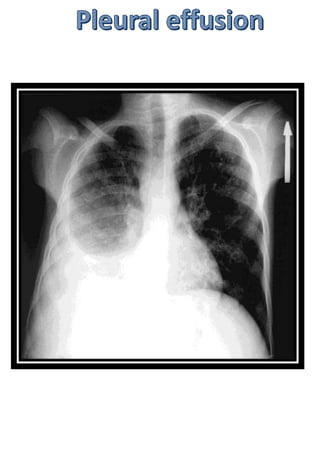

Chest x ray lateral view

Commonly done in older days

Highest point of diaphragm

located anteriorly

Diaphragm dips down from

anterior to posterior

Most dependent part of pleural

cavity lies posteroinferiorly.

© DR RALLAPALLI

SPANDANA MD 10/10/2020

Posterior costophrenic recess.

Fluid collection (pleural effusion)

Normal finding in a lateral chest x

ray